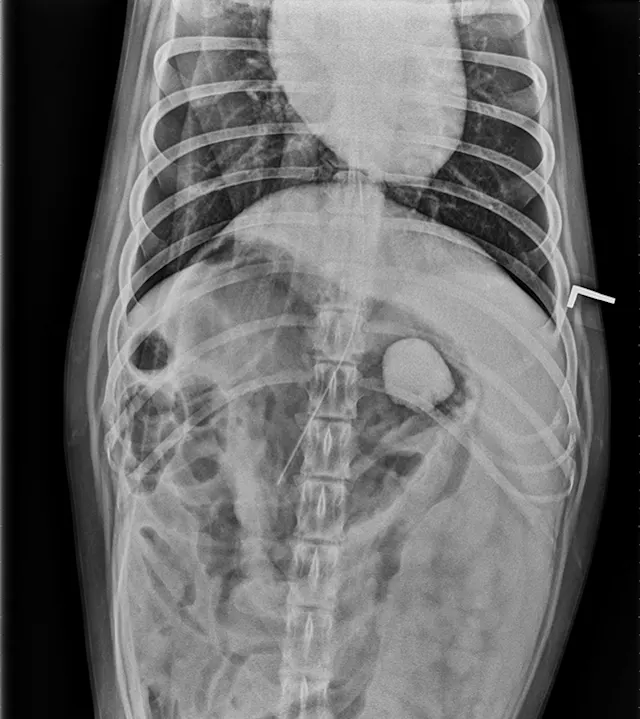

FIGURE 1A

Lateral view. Abdominal radiographs showing a rock foreign body that appears to be located in the small intestine. No small intestinal foreign body could be located on abdominal ultrasound; however, a shadowing foreign object was possibly located in the stomach.